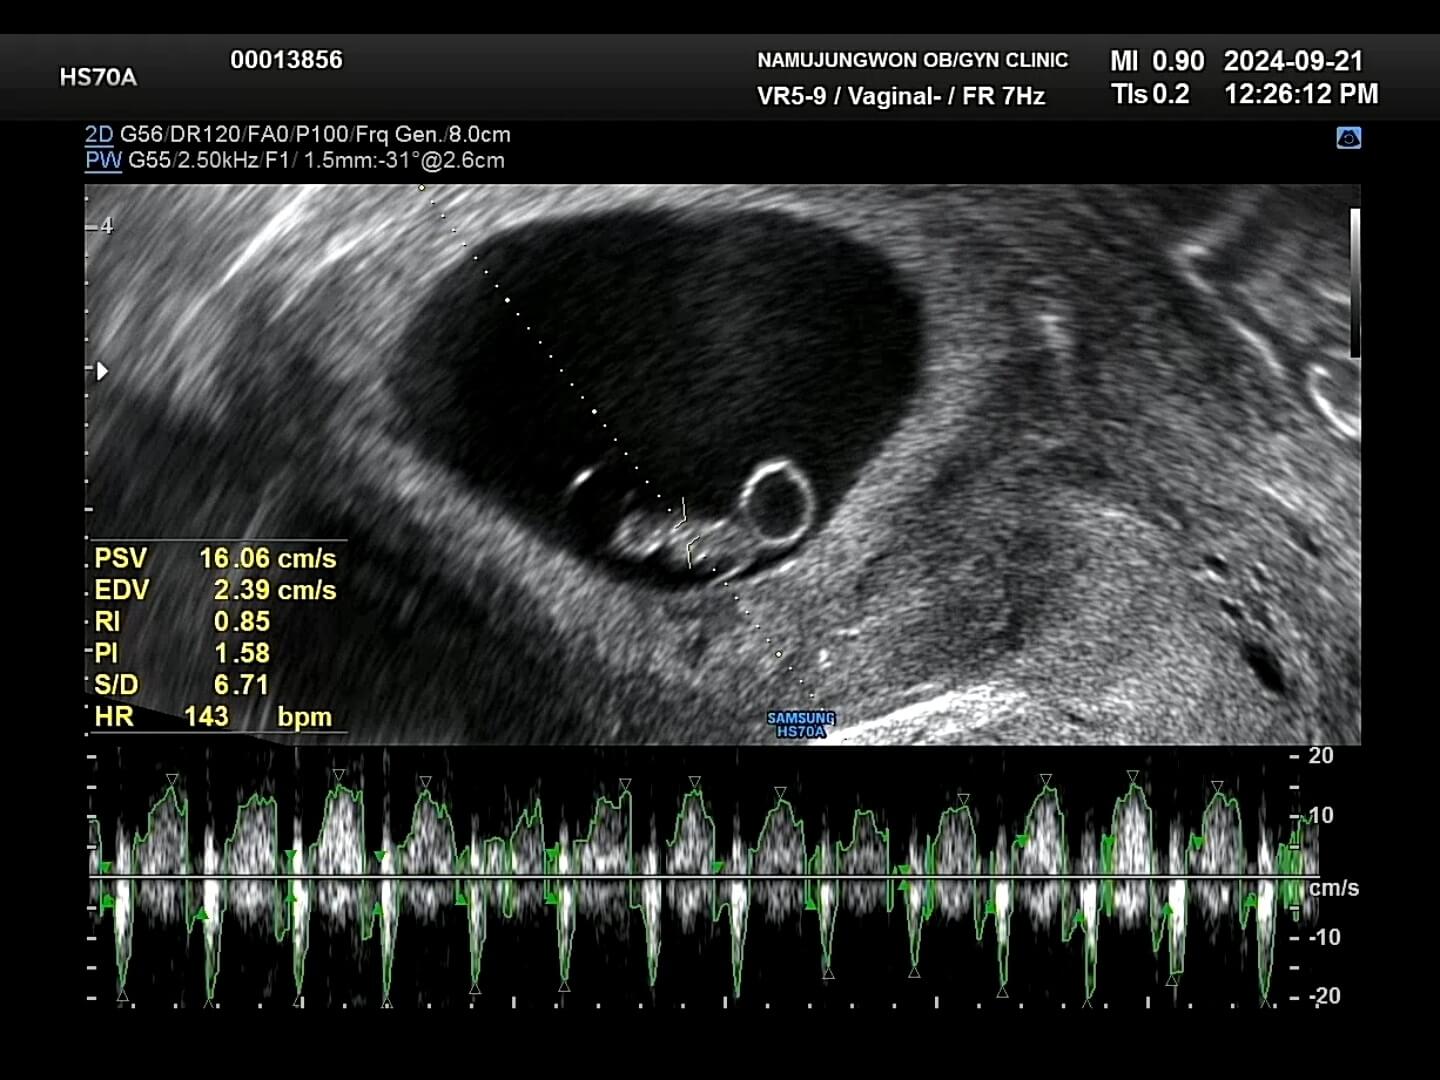

7주차-초음파 그래도 병원에 가서 아기 모습을 보니 너무 신기하고 귀여웠어요. 7주차되는 날 사진인데, 저 동그랗게 보이는게 난황이고 옆에 보이는게 배아라고 하시더라구요. 배아는 난황에 있는 영양분을 섭취하면서 무럭무럭 자라난다고 합니다!

7주-심장박동 7주차 우리 꾸미는 심장박동 143bpm으로 정상범위로 아주 잘 자라고 있었어요. 임신 초기에는 워낙 불안정한 시기이기 때문에 뱃속에 아기가 잘 있는지를 보통 '임신 증상'으로 확인을 하곤 했습니다. 컨디션이 너무 안좋아서 '아, 우리 꾸미가 뱃속에 잘 있구나!' 라고 생각했어요.